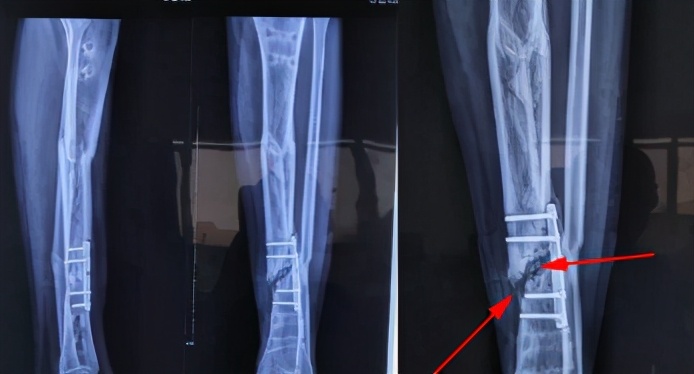

骨折断端局部血液供应情况:骨折部位有充足的血液供应被认为是最重要的因素之一。所以血供较差的部位如:腕舟骨,胫骨中下段,股骨颈等,骨折愈合较慢,很容易形成骨折不愈合。

断端稳定很重要:力学稳定是骨折正常愈合的重要条件。手术的目的除了复位骨折断端外,另一个重要作用就是维持断端稳定,为骨折愈合创造良好环境。

手术因素:手术中骨膜剥离过多,血运破坏多,软组织保护欠佳,断端间隙过大,固定后稳定性不够,均会影响骨折愈合。